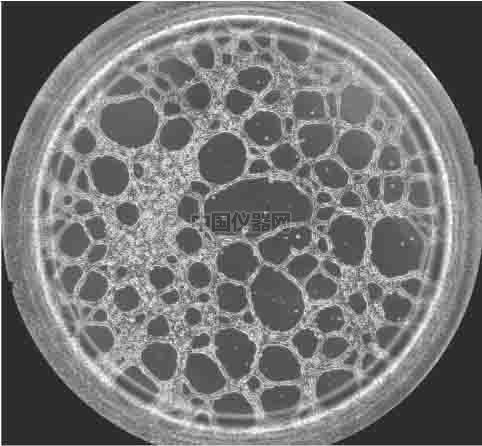

圖一 血管生成鏡檢圖 一.實(shí)驗(yàn)材料和實(shí)驗(yàn)方法 1.實(shí)驗(yàn)材料